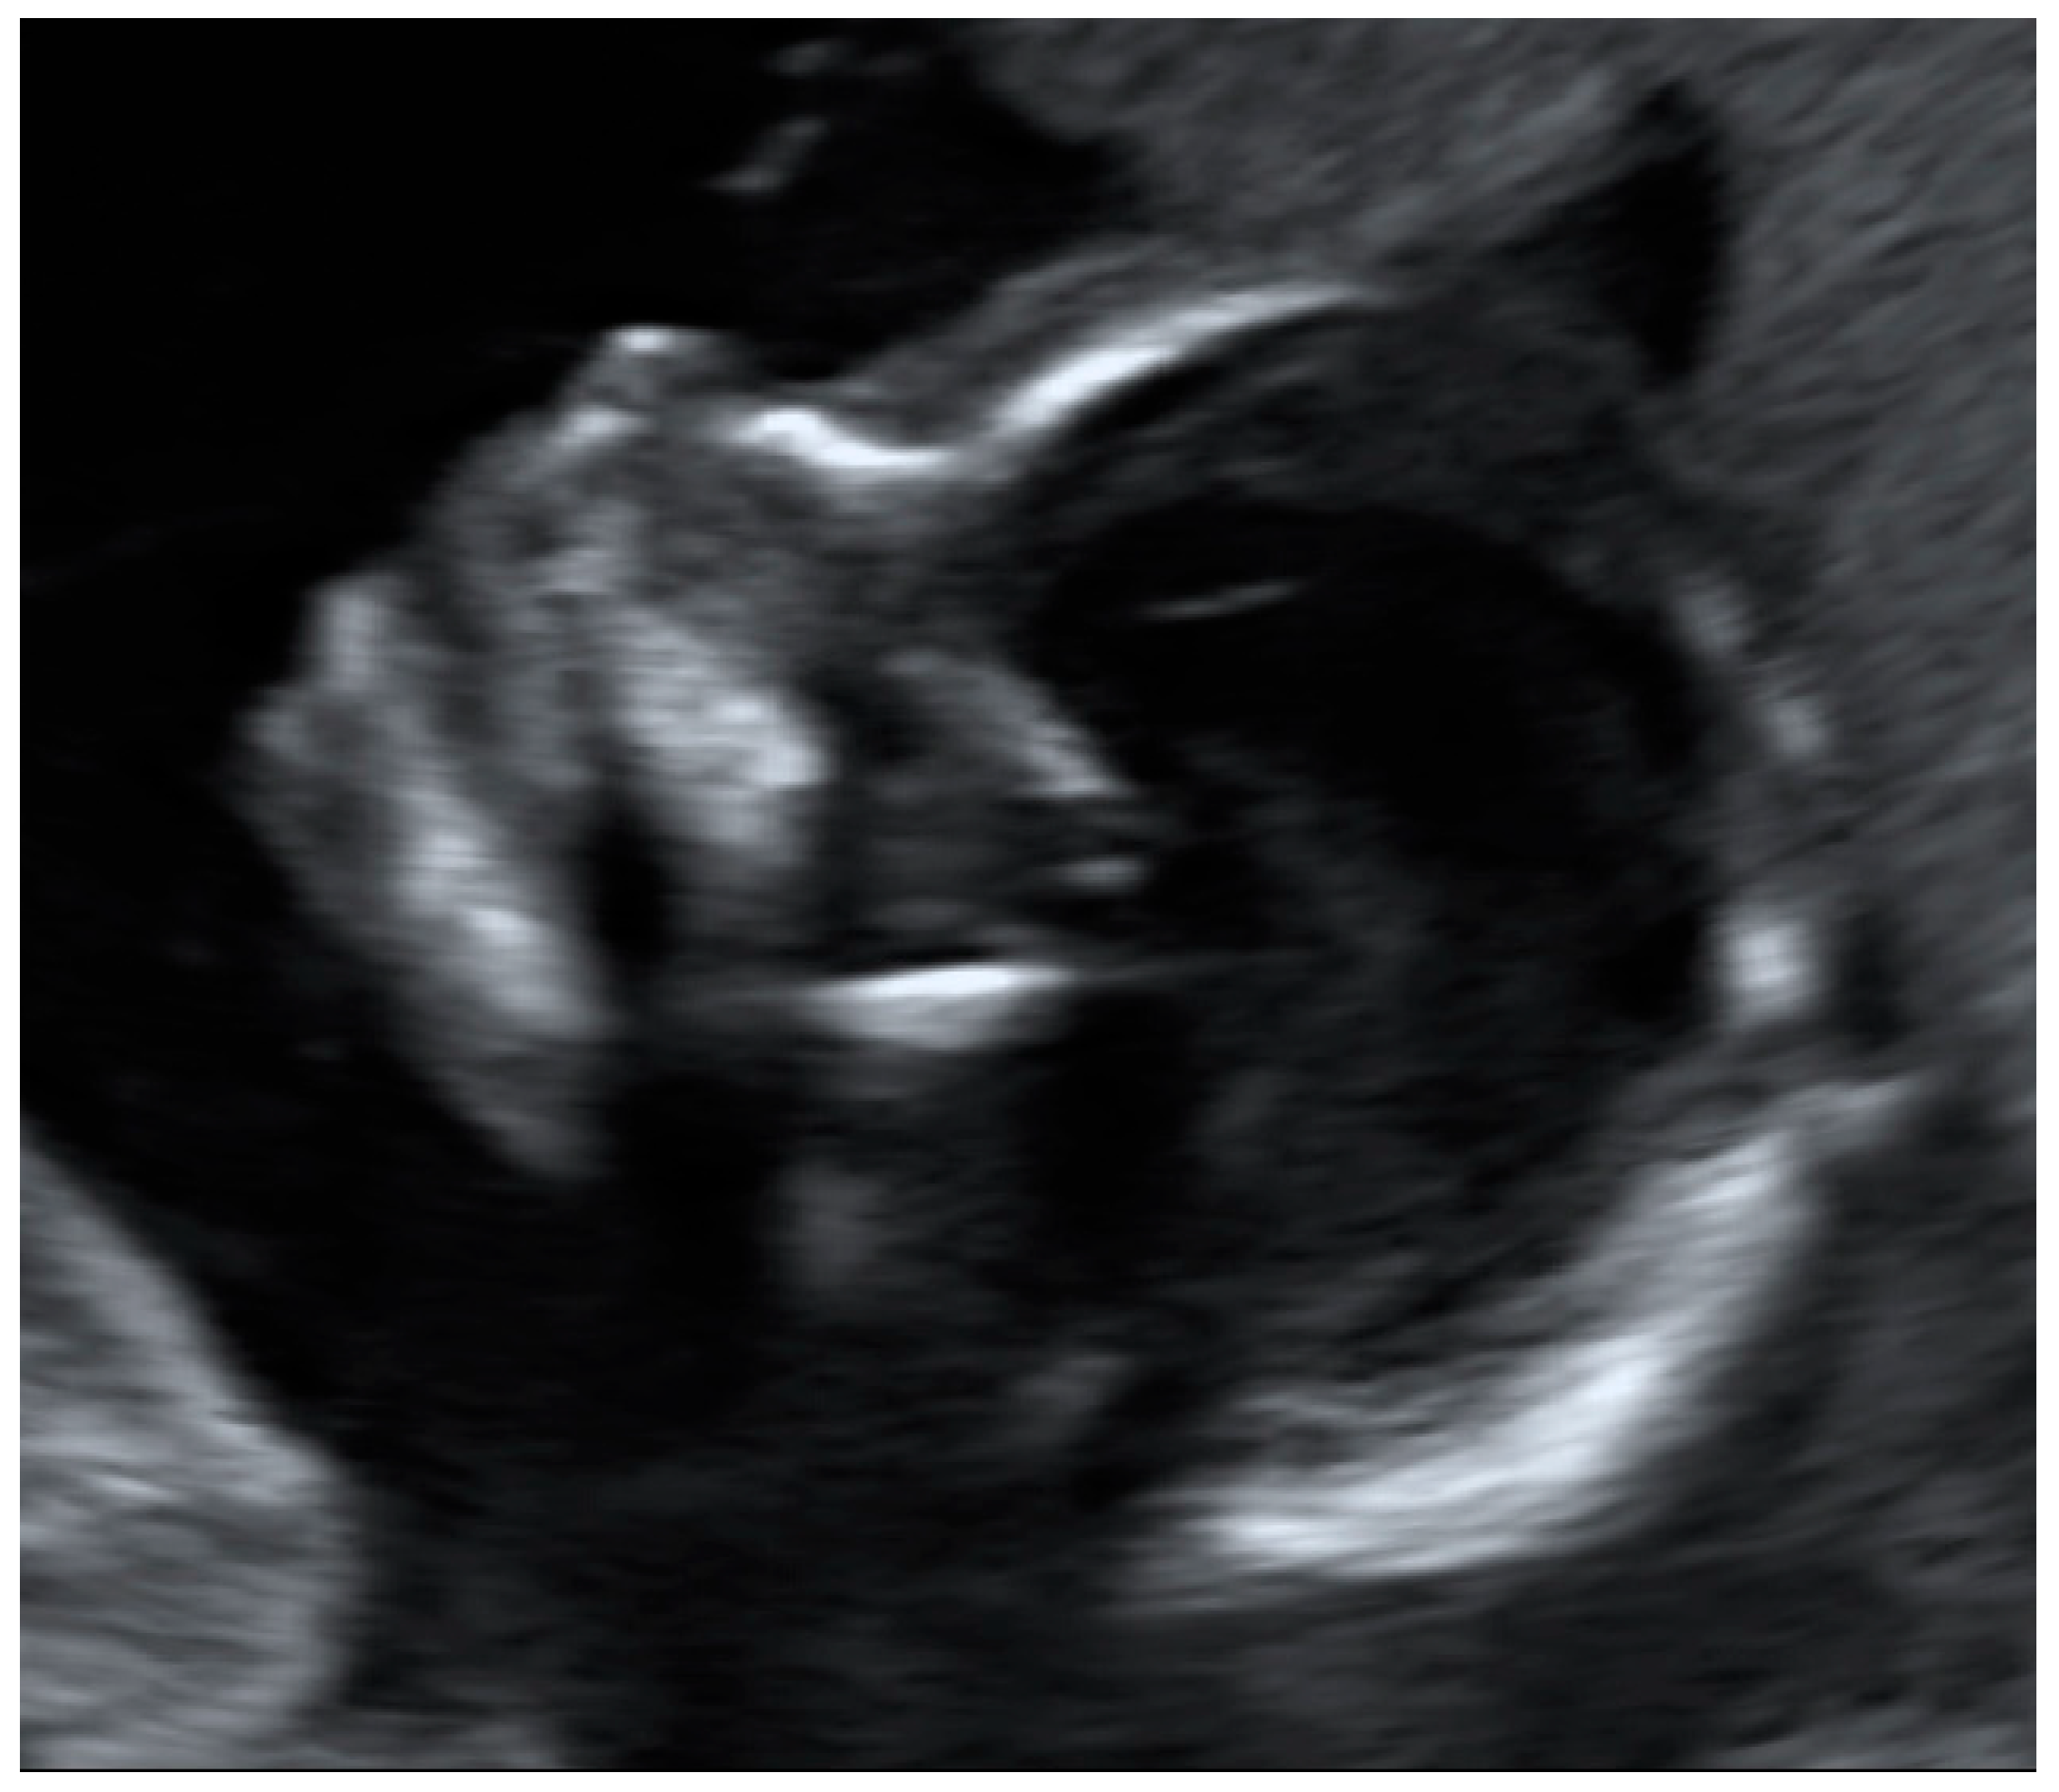

The heartbeat was correctly captured by more than half of the participants (n = 24, 52.2%; Table 3) (Figure 2a,b).

Figure 2.

(a) Example of an image obtained by a study participant in cohort A, showing the heartbeat (satisfactory presentation). (b) Example of an image obtained by a study participant in cohort B, showing the heartbeat (satisfactory presentation).